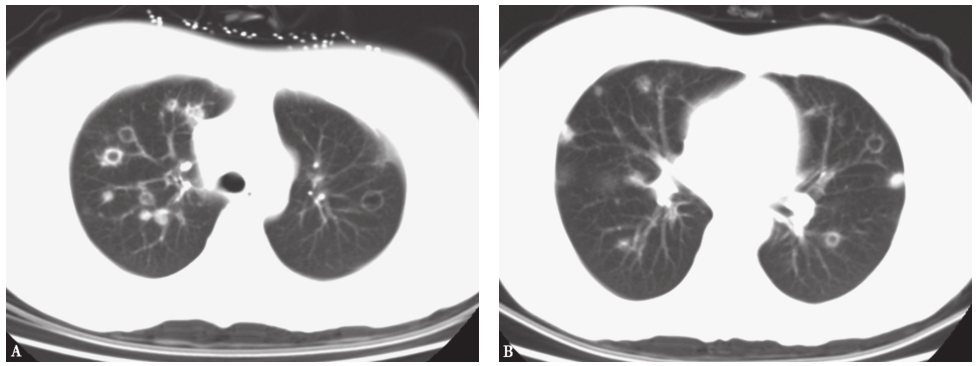

发病第4天,患者于当地医院就诊,胸部CT提示双肺多发结节样改变(图1)。发病第32天,患者转至当地上级医院就诊,胸部CT提示病变较前加重,可见双肺多发大小不一的结节影,部分呈反晕环状,边缘尚清(图2)。

图1发病第4天胸部CT表现

图2发病第32天胸部CT表现